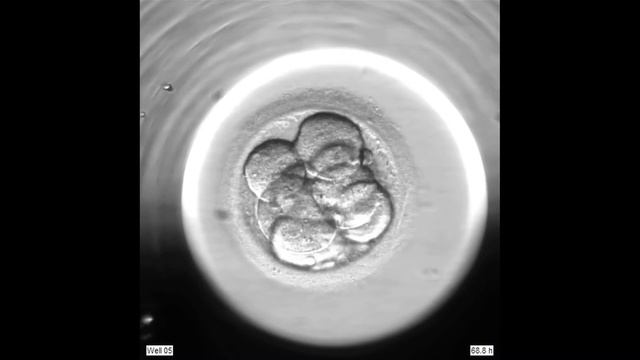

Благодаря передовым технологиям, репродуктивный центр New Hope Fertility использует EmbryoScope (Эмбриоскоп) для непрерывной оценки развития эмбрионов д...